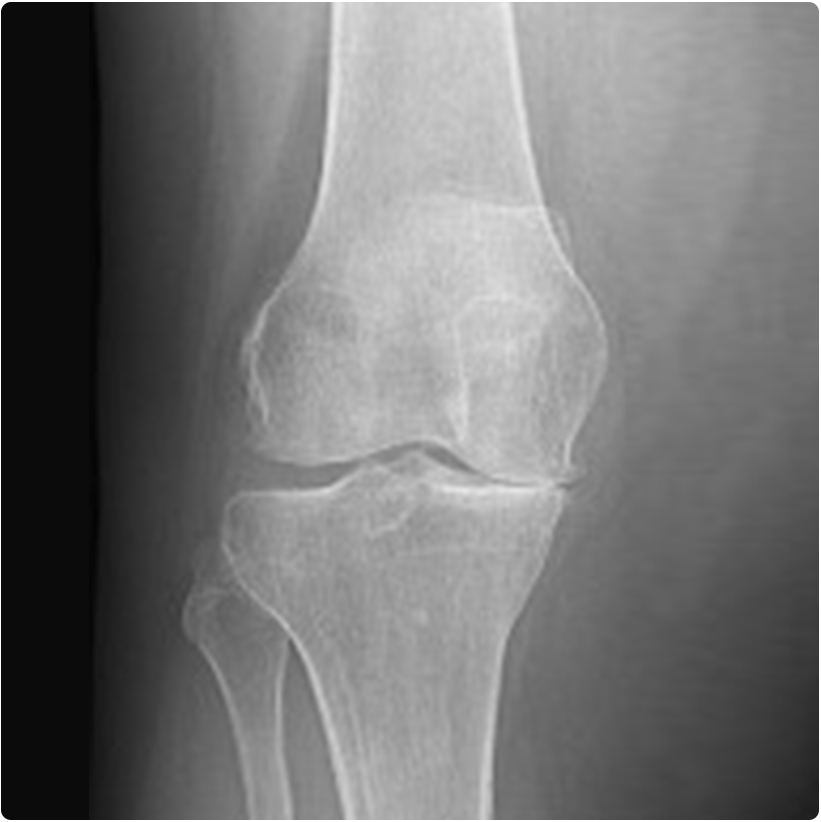

Dizde osteoartrit (kıkırdağın aşınması-kireçlenme) orta – ileri yaşlarda sık görülen ve kişinin yürümesine ve diz hareketlerine engel olan, ağrı nedeniyle yaşam kalitesini düşüren sağlık sorunlarından biridir. Kıkırdakta meydana gelen aşınma bazen romatizmal sebepler veya eklem içi kırıklar sonrası oluşurken, çoğunlukla sebebi bilinmeyen osteoartrit ile karşılaşılmaktadır.

Dizin tamamına ilerlememiş, belli bir bölgesini yaygın olarak tutmuş osteoartritte tam diz protezine alternative olarak kısmi (yarım) diz protezi yapılabilmektedir. Bu ameliyat daha küçük bir kesiden yapılan, hem dizin bozulan eksenini düzelten, hem de aşınmış kıkırdak bölgesine konan protezle sorunu ortadan kaldıran bir işlemdir. Ameliyat için doktorunuzun muayene ve incelemeleriyle karar vereceği bazı ön şartlar vardır. Bu şartlara uygun olan hastalarda titiz uygulama ile çok iyi sonuçlar alınabilmektedir.